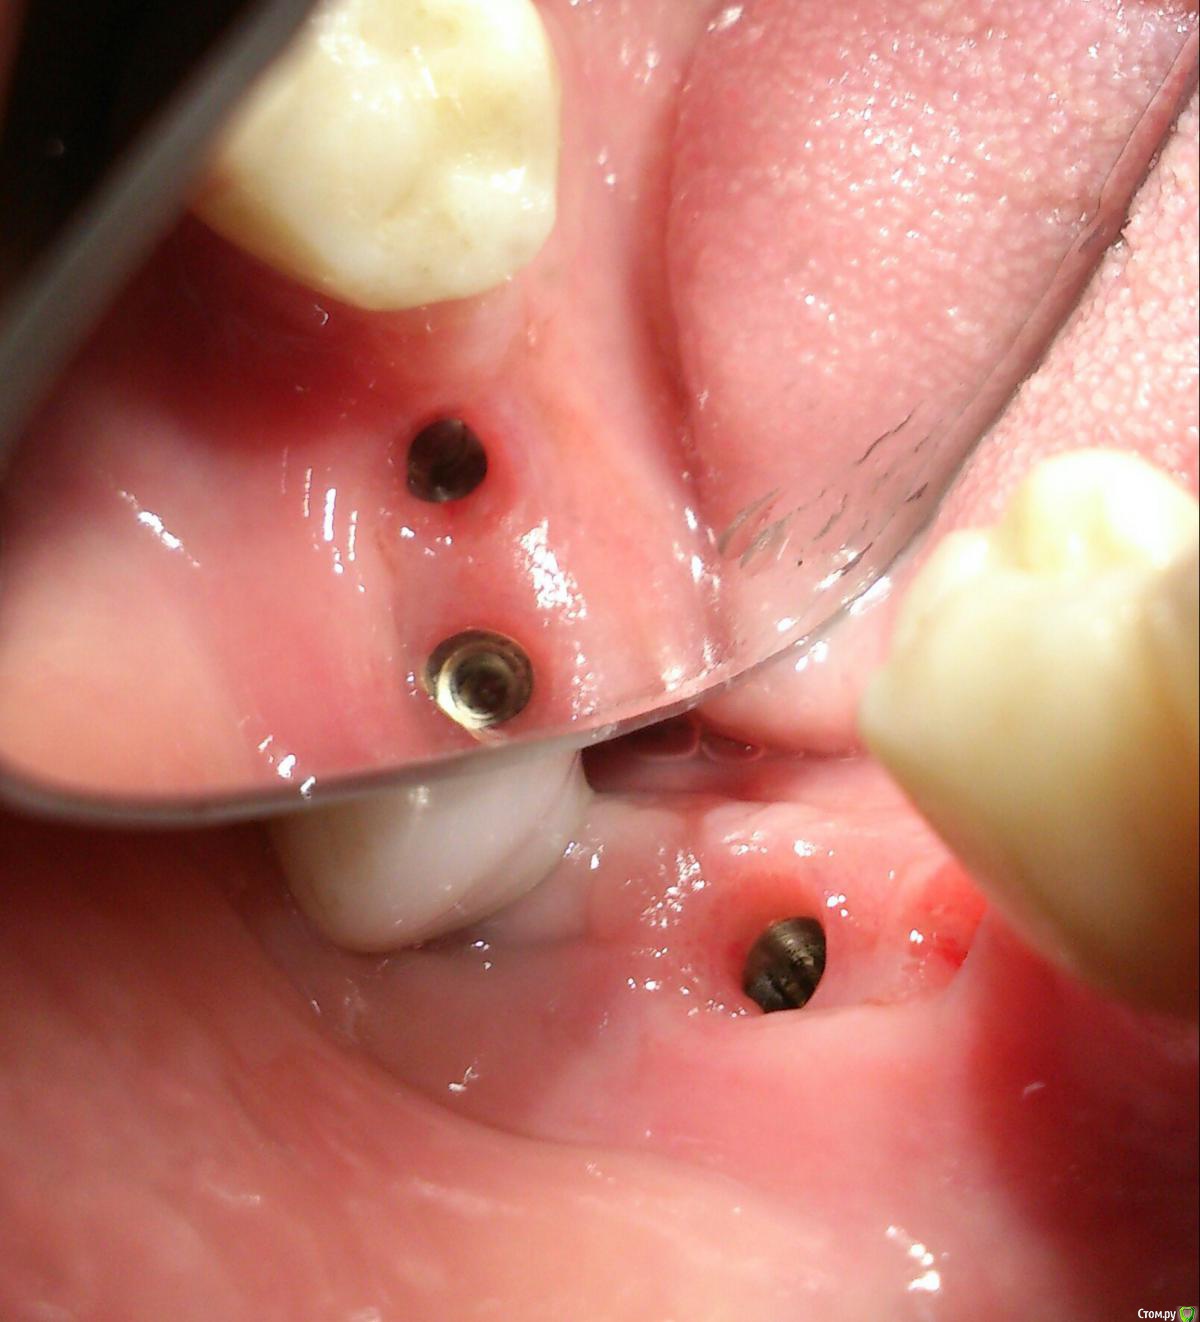

andrey_1965 Опубликовано 21 декабря, 2015 Поделиться Опубликовано 21 декабря, 2015 Ну как результат ?1.-диэпителизация подворот лоскута очень удобно,но опасно для резбы через неделю.язычно-механическая травма через 10 дней через 3недели. На временных доформирую рельеф.2. вроде ничего нештатного через 2недели A-PRF через 5недель убрал все,закрыл мембраной A-PRF две поперек,одна в доль через неделю через 13дней через 21день. Следующий осмотр будет на сроке 5 недель(думаю все сравняется) 3. через неделю 2недели 3недели,на дистальных отмываю помойку4 недели Ссылка на комментарий